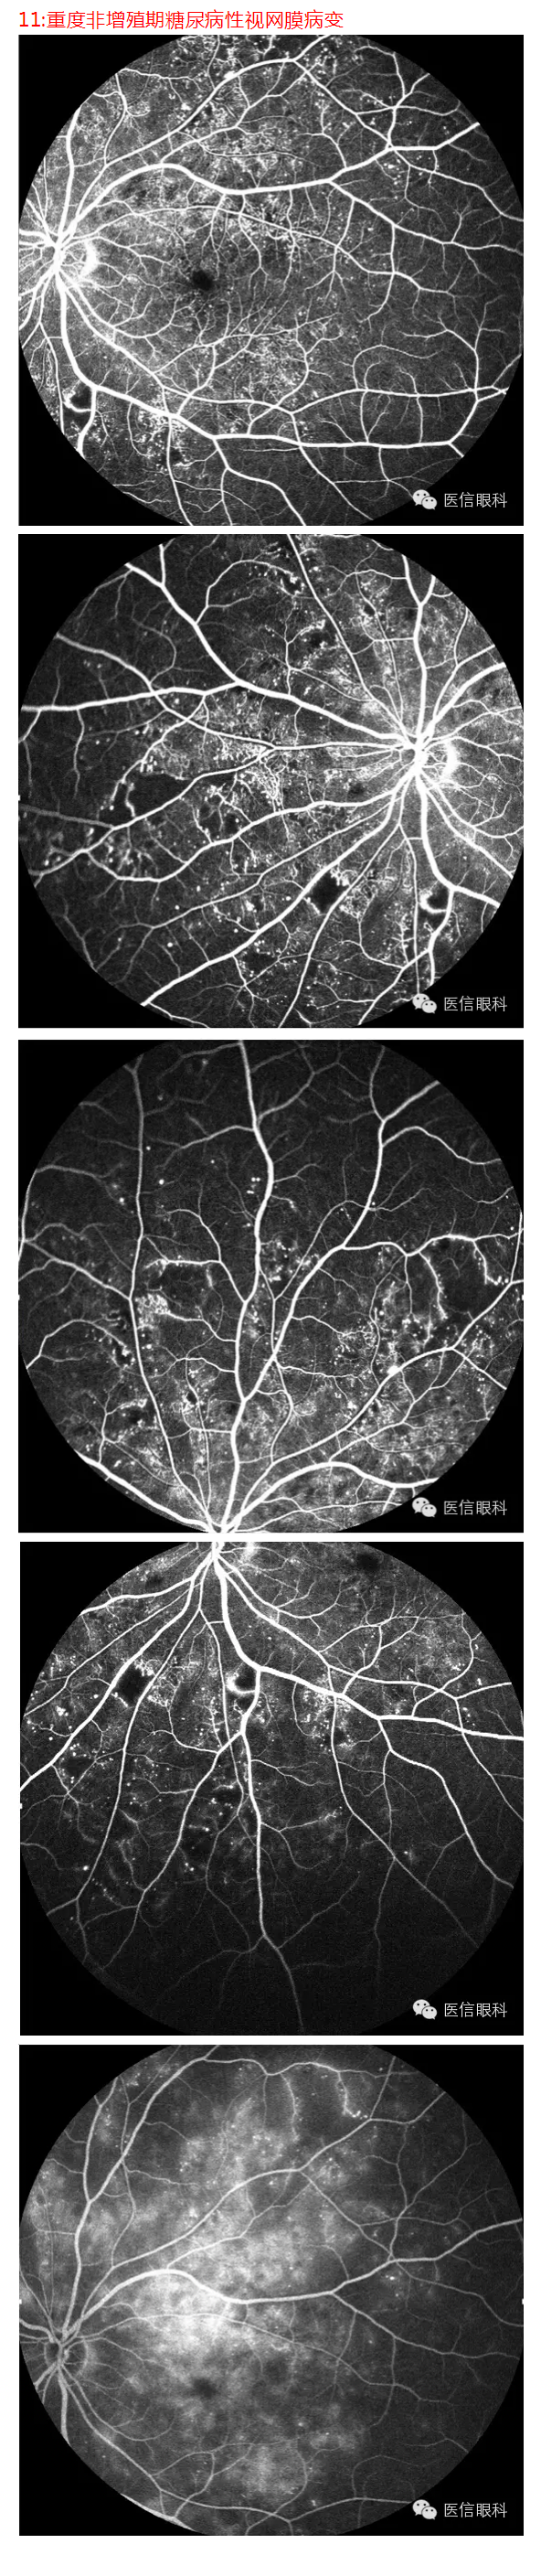

常见眼底病荧光血管造影表现(多图一)